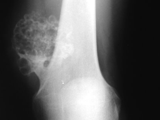

Synovial chondromatosis

Synovial chondromatosis